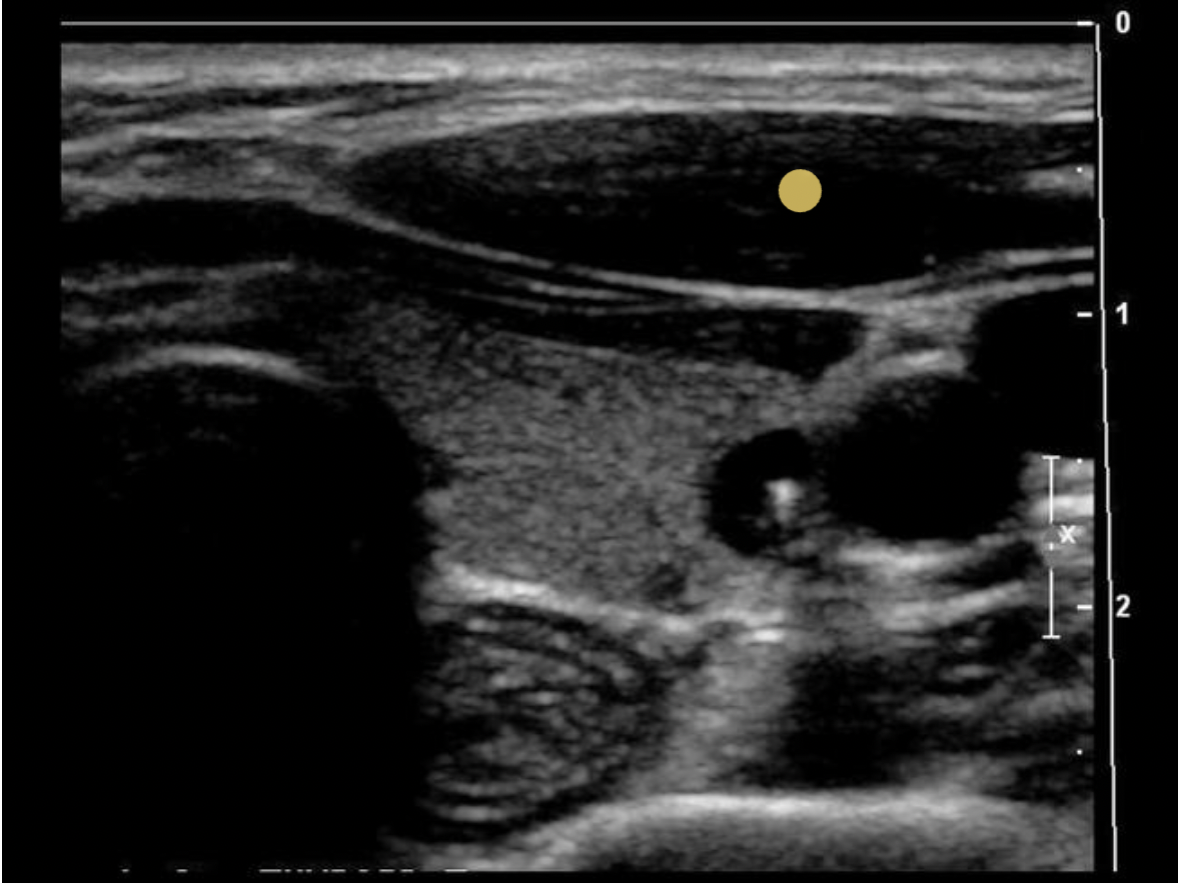

What is indicated by the yellow arrow?

C. esophagus

The arrow indicates the esophagus. Note the rings of tissue seen with normal Gl tract structures.

Which structure is visualized posterior and medial to the left lobe of the thyroid gland?

The strap muscles and the omohyoid muscle, one of the strap muscles, are anterior to the gland. The sternocleidomastoid muscles are anterior and lateral.

The longus colli muscles are on either side of the spine, posterior to the thyroid lobes. The esophagus is posterior and medial to the left thyroid lobe.